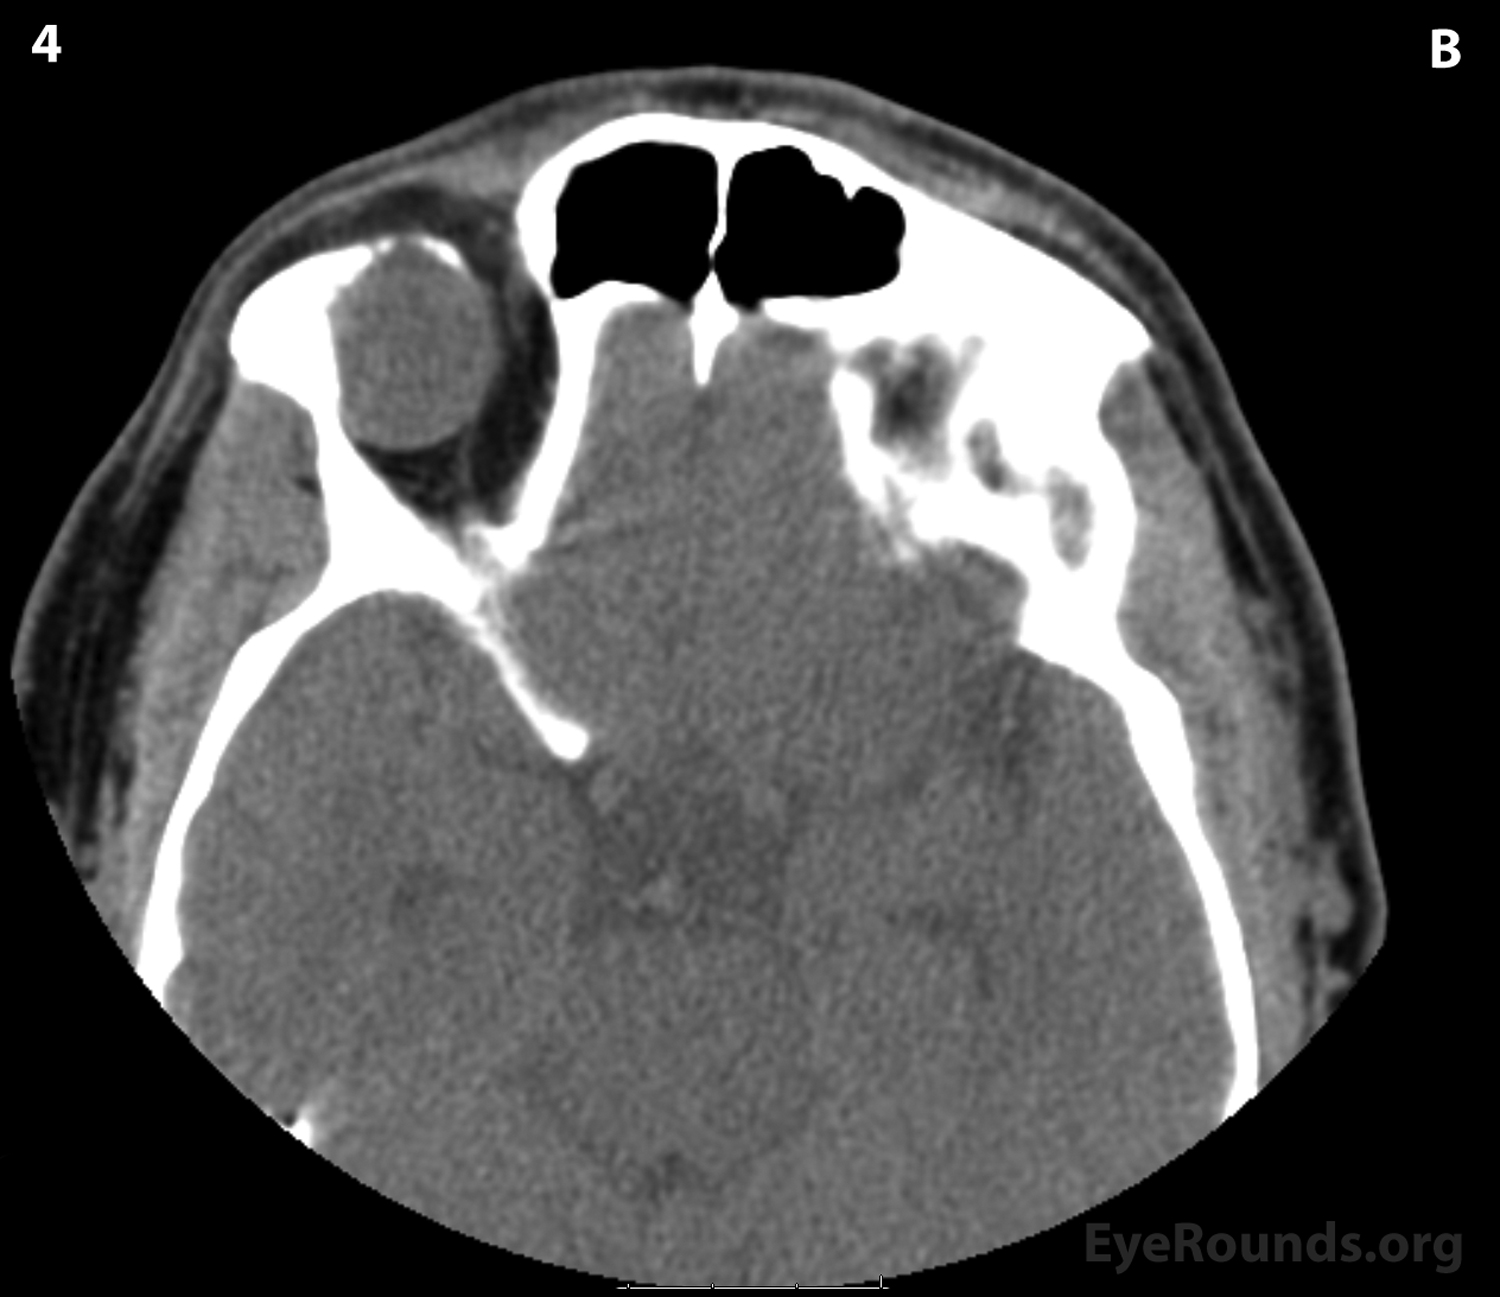

CT of orbits without contrast. (A) Coronal section

Figure 2: CT of orbits without contrast. (A) Coronal section; (B) Axial sections (superior to inferior 1-6): A circumscribed, encapsulated, soft tissue attenuation mass lesion in the superolateral right orbit can be seen eroding into the orbital roof and lateral right frontal bone. The mass appears to be compressing the superolateral globe and displacing the globe and superior and lateral recti anteriorly.